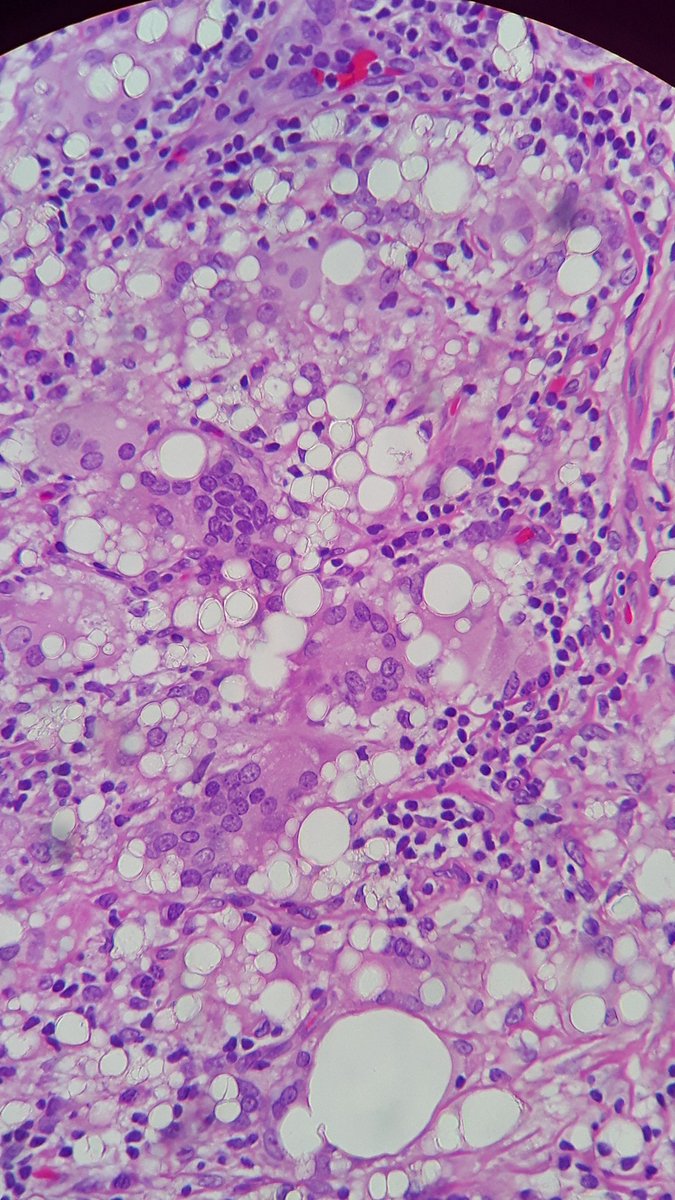

♀ axilar lymph node. When you cut it, translucent & sticky material. Your guess? #grossognosis @SEAP_IAP

Micropics for all the #pathtcuriosus & @ariella8